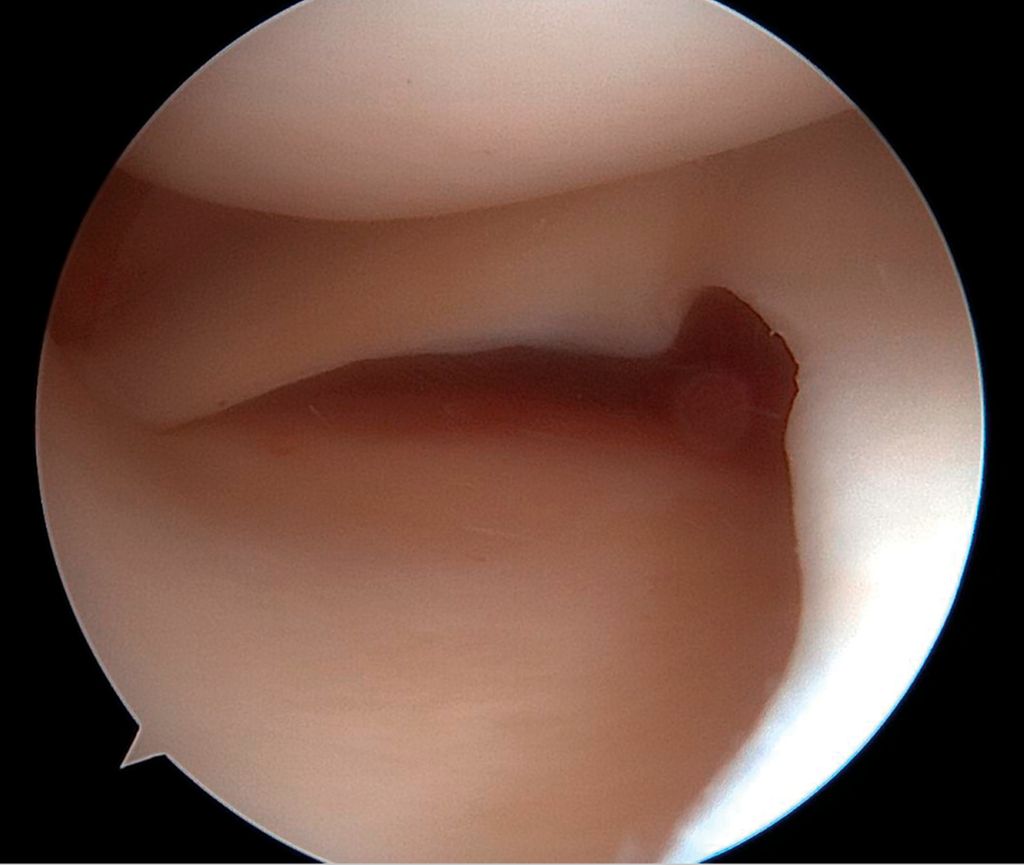

Arthroskopische Instabilitätszeichen: „floating meniscus“ und „drive-through sign“

In einer Level-I-Studie an Patient:innen mit kombinierten VKB- und Grad-II-MCL-Verletzungen (nach Fetto und Marshall) und „Floating-Meniskus-Zeichen“ zeigte die Patientengruppe nach MCL-Augmentation mittels gestielter autologer Gracilis-Sehne signifikant weniger VKB-Revisionen, eine geringere residuale MCL-Laxität sowie bessere patient:innenberichtete Outcome-Scores nach 24 Monaten im Vergleich zu Patient:innen mit isolierter VKB-Rekonstruktion und konservativ behandeltem MCL. Die Abbildung 1 zeigt das „Floating-Meniskus-Zeichen“, ein arthroskopisches Zeichen der medialen Instabilität, bei dem sich der mediale Meniskus vom tibialen Plateau abhebt, infolge einer meniskotibialen Läsion des tiefen Innenbandes. Aufgrund einer zusätzlichen Läsion des oberflächlichen Längsbandes kommt es zu einer medialen Gelenköffnung, die als „medial drive-through sign“ bezeichnet wird.

Im Folgenden werden nun die beiden Rekonstruktionstechniken zur operativen Therapie der symptomatischen AMRI dargestellt. Wie bereits erwähnt, sollte insbesondere bei chronischer Instabilität oder in Revisionsfällen eine Beurteilung der Beinachse mittels Ganzbeinstandaufnahme erfolgen, da bei knöcherner Valgusfehlstellung eine achskorrigierende Osteotomie vor einer Bandrekonstruktion in Betracht gezogen werden sollte.